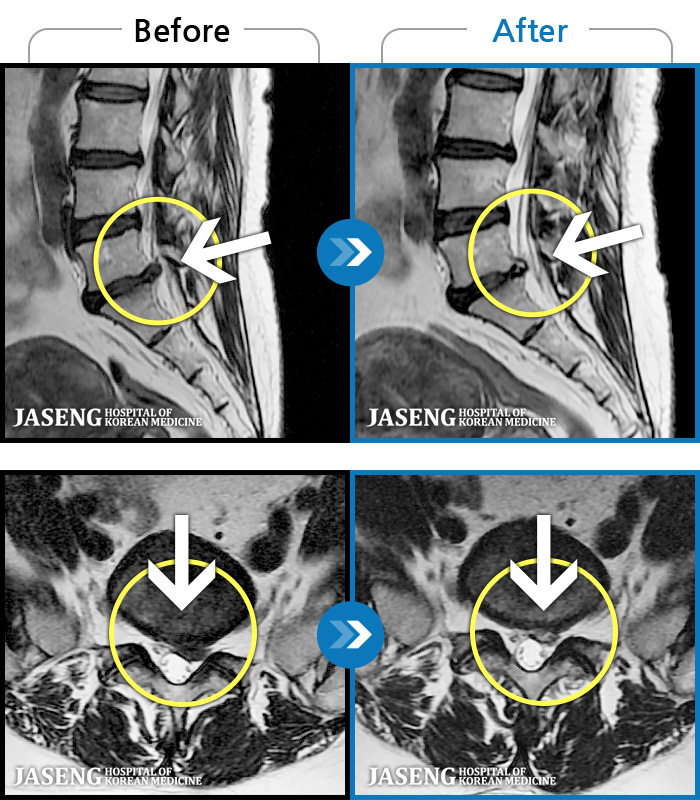

MRI ġ

1,237 MRI ũ ʸ Ȯϼ.